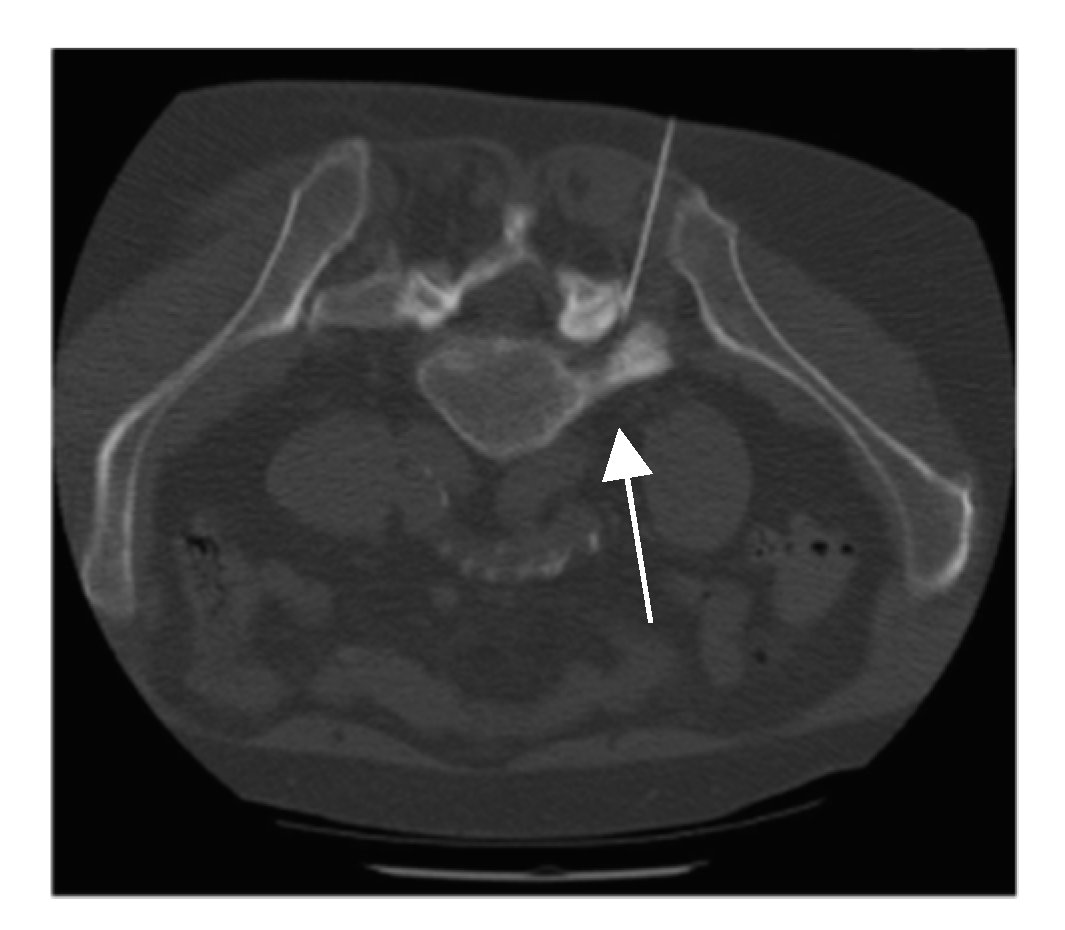

2.2. Intervention